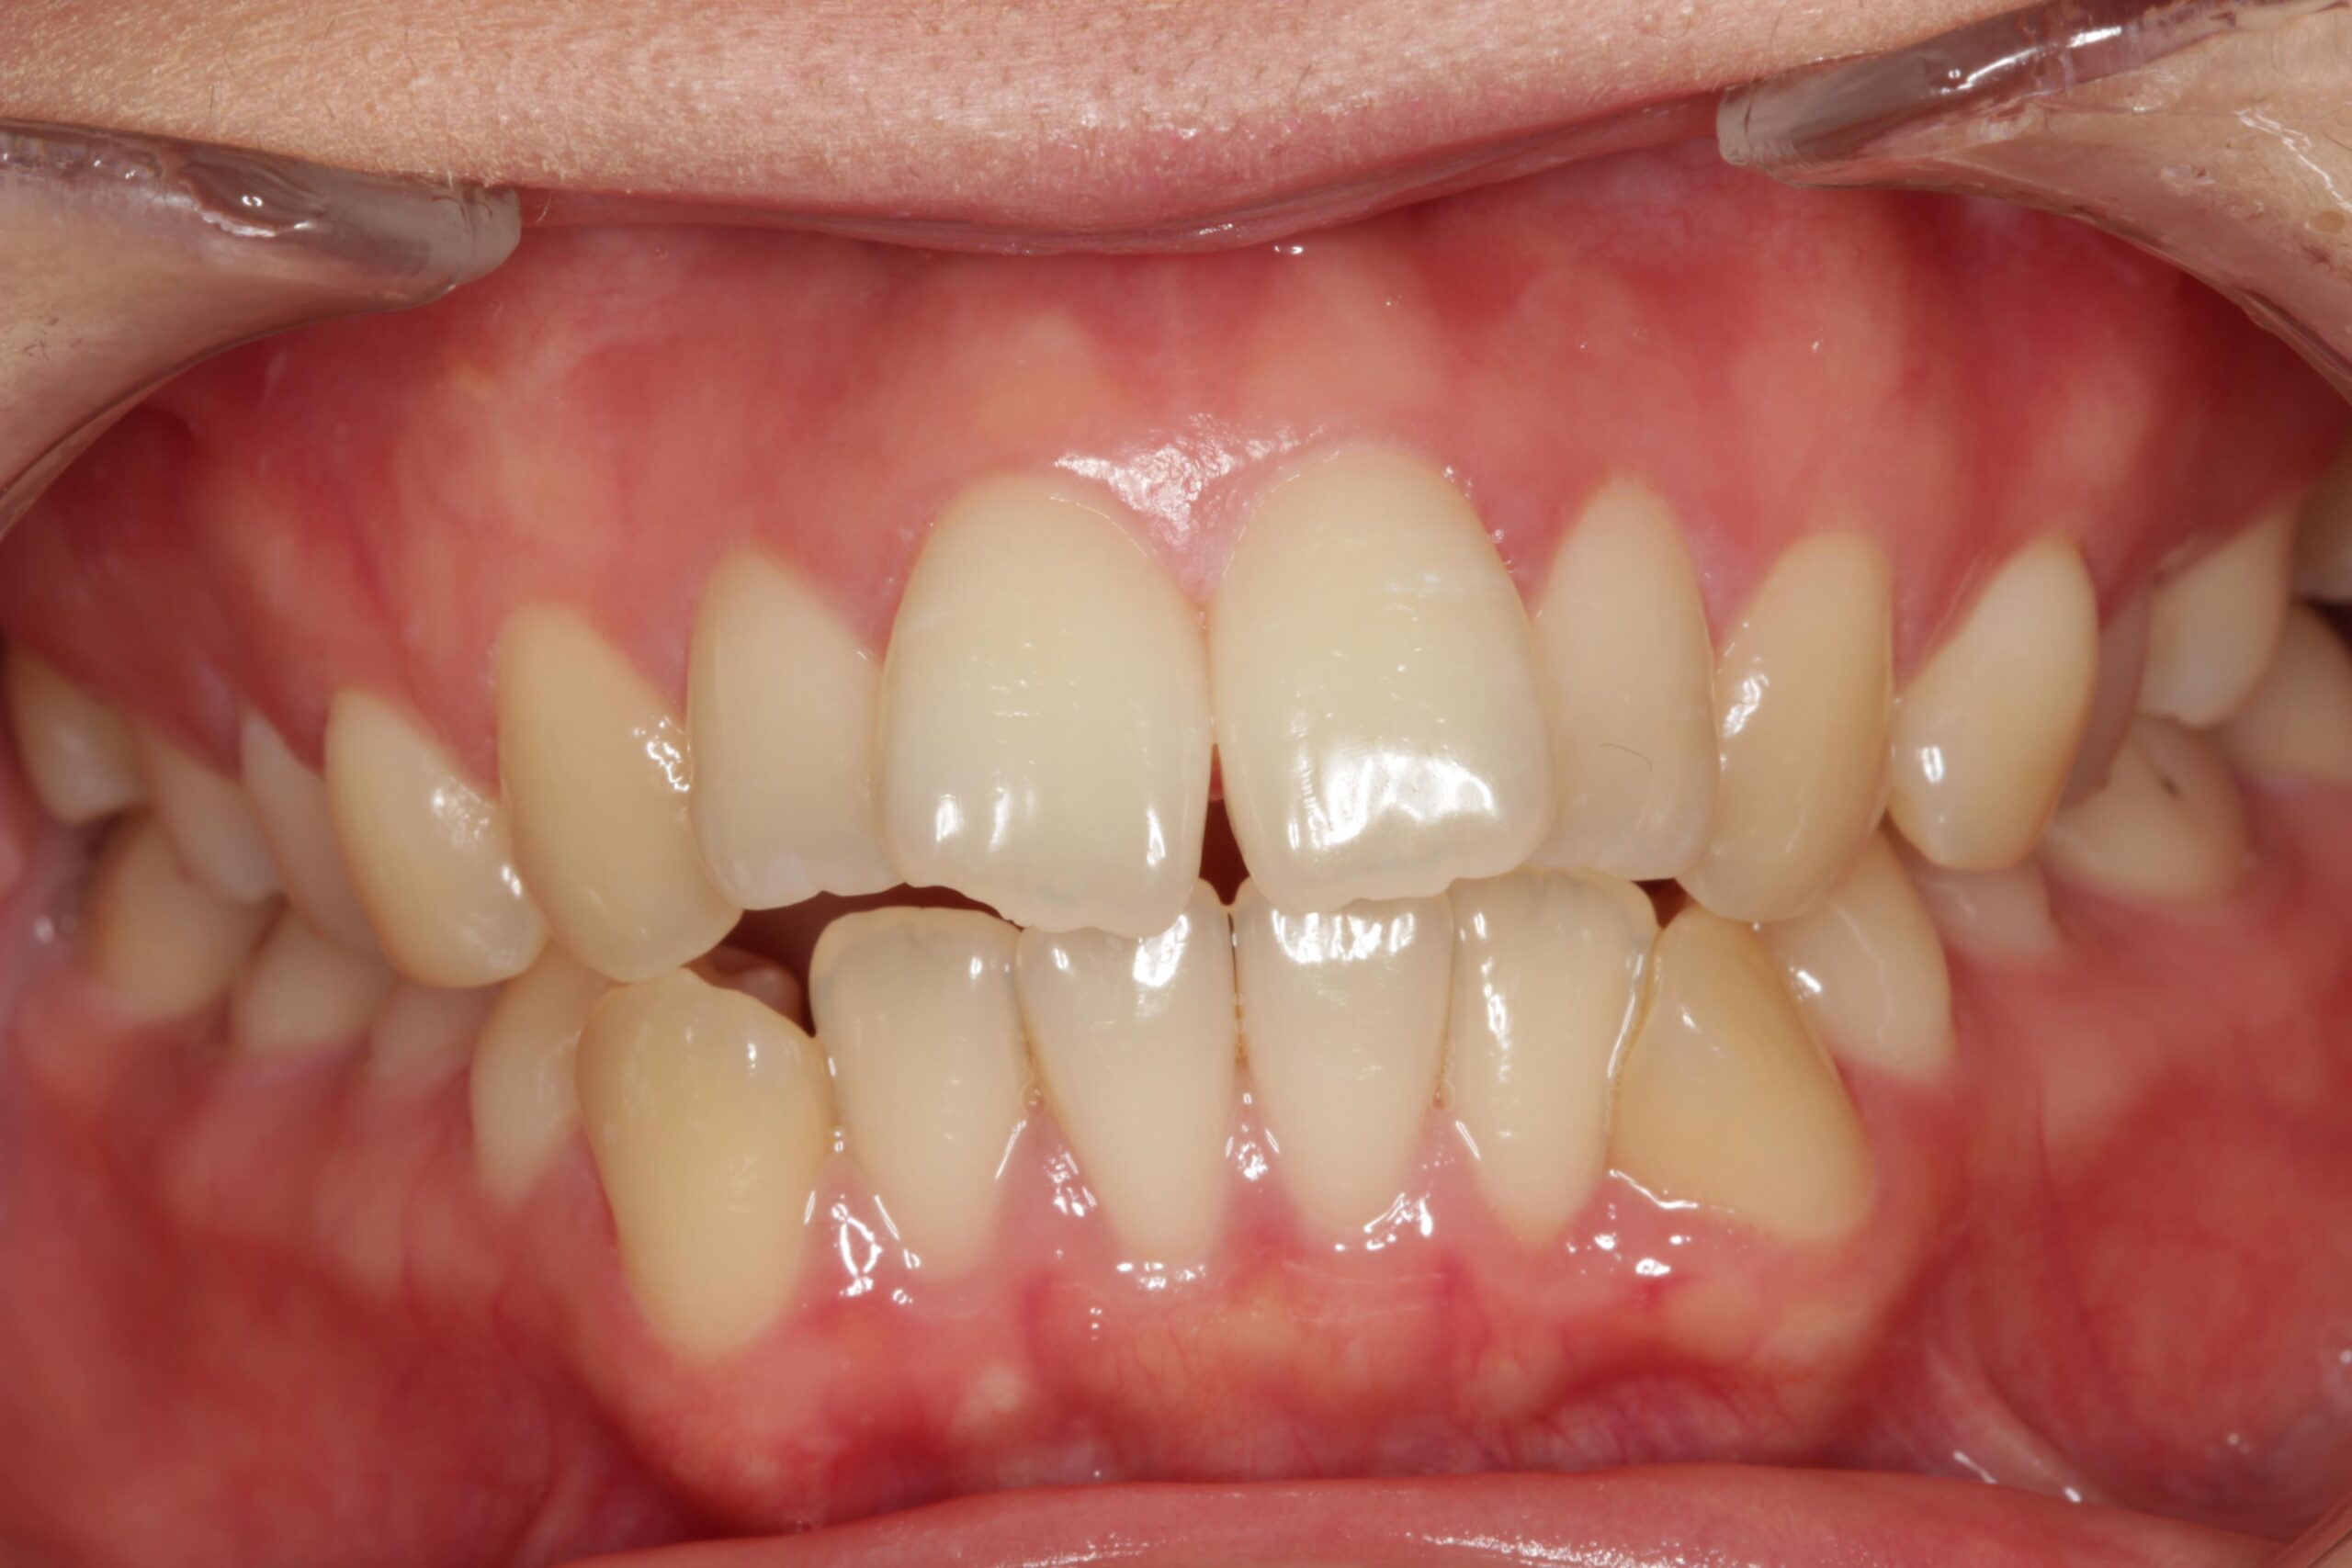

上の前歯が他の歯に比べて前に突き出ている状態です。

見た目のお悩みに限らず、口が閉じにくいためお口の中が乾燥して菌が繁殖し、むし歯や歯周病のリスクが高まります。